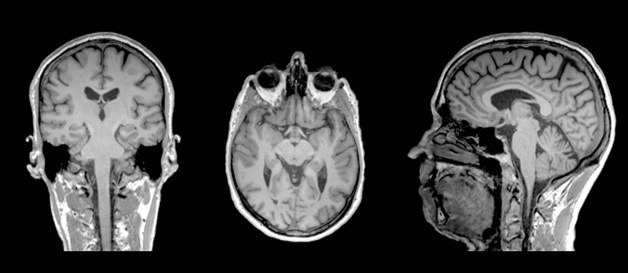

plan coronal

ou frontal

plan horizontal

plan sagittal